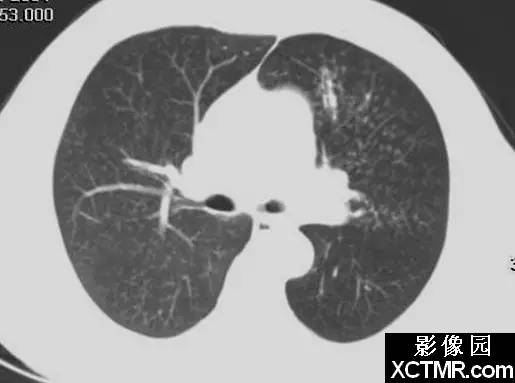

影像表现:印戒征见于胸部CT扫描。它是由一小圆形软组织密度影邻接一围绕大圆形低密度空气影的环状软组织密度影构成。

说明:在横断面CT扫描上,环状软组织密度影代表扩张的支气管壁,圆形低密度空气影代表扩张的支气管内气体。与环邻接的圆形软组织密度影代表与扩张支气管伴行的肺动脉的横断面影像。

讨论:印戒征是支气管扩张患者的CT表现。支气管扩张定义为不可逆性支气管异常扩张。扩张的支气管一般在中等大小的支气管最广泛。同时,可以发生支气管肌肉萎缩,支气管壁破坏,支气管周围炎症和纤维化。由于纤毛活动减弱和支气管动力学异常,大量粘液聚集在这些扩张的支气管内。

支气管扩张常由于坏死性病毒性或细菌性支气管炎后支气管壁损伤引起,常发生在婴幼儿期。支气管扩张也可发生在阻塞的支气管远端,当分泌物聚集在阻塞支气管的远端导致它们扩张。进展期肺纤维化或放射性肺损伤也能引起支气管扩张。囊性纤维化;通气压增高,例如正压通气;纤毛功能紊乱,如Kartagener综合症以及各种免疫缺陷都同样与支气管扩张有关。

支气管扩张一般分为三种形态学类型。柱状支气管扩张,最轻的形式,特征是支气管轻度均匀扩张。静脉曲张样支气管扩张是指支气管中度扩张,呈不规则串珠样。囊状扩张是最严重的,支气管显著囊样扩张,伴有数量不等的分泌物池。

支气管扩张的临床表现常为非特异性的。慢性咳嗽,过量痰,反复肺部感染,咯血都可以出现。尽管胸部平片可以显示扩张的支气管,CT可以提高我们发现支气管扩张的能力。事实上,CT已经取代支气管造影,成为评估支气管扩张可能的研究选择。薄层CT对发现支气管扩张的敏感性为87%-97%,特异性为93%-100%。

支气管扩张的胸部平片表现包括扩张的充气支气管,支气管壁增厚,肺实质体积减小,支气管聚集。也能见到由于肺炎或纤维化所致的肺透亮度异常。在薄层CT可见到支气管扩张,缺乏支气管尖端变细,在胸膜1cm内见到支气管,支气管壁增厚和印戒征等。支气管与动脉比率随不同参数而变化,例如CT扫描的海拔高度,因此,仅发现支气管直径大于相邻动脉不足以诊断支气管扩张。

以CT为基础诊断支气管扩张有几个缺陷,包括呼吸运动或心脏搏动所致的运动伪影,与层厚和窗相关的技术因素。因此常需要用薄层CT来诊断支气管扩张。